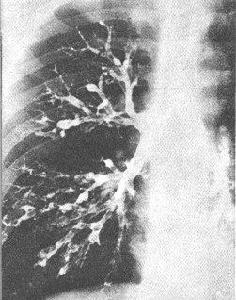

4.支氣管造影 支氣管碘油造影是傳統的確診支氣管擴張症的方法,可確定病變的存在,明確病變的部位性質及範圍,可為外科手術指征和切除範圍提供重要的參考依據。造影前要控制急性炎症,儘可能減少痰量,造影后應採取體位引流,使造影劑能及時排出。近年的研究表明,HRCT或螺鏇CT檢查已有取代支氣管碘油造影的趨勢。